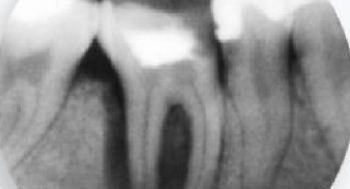

Oferujemy wysokiej jakości badania diagnostyczne, takie jak: RTG punktowe, pantomogram, cefalometria, tomografia CBCT, cyfrowy skan zębów oraz dentystyczny protokół fotograficzny.

Efektywne leczenie stomatologiczne w większości przypadków wymaga dokładnej diagnostyki, opierającej się na zobrazowaniu stanu uzębienia, kości szczęki czy żuchwy. Jednym z popularnych sposobów diagnostyki stomatologicznej jest zdjęcie pantomograficzne, czyli pantomogram. Pozwala ono uzyskać precyzyjny obraz struktur, z odwzorowaniem wszelkich krzywizn i ewentualnych nieprawidłowości. Zaawansowaną diagnostykę zapewnia tomografia komputerowa CBCT, która oferuje obrazowanie w technologii 3D.